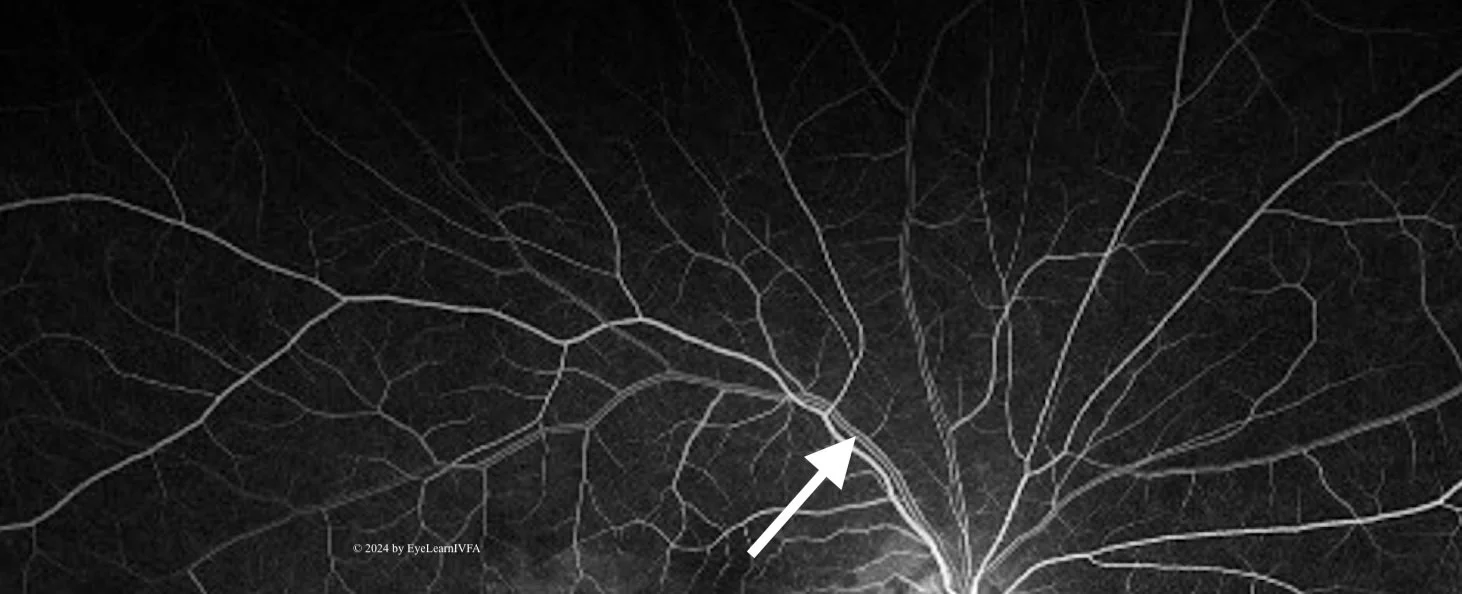

Phase 3: The Early Arteriovenous Phase (1-2 seconds post-arterial phase)

• Veins begin filling in this phase.

• Look for laminar and trilaminar venous flow.

Arrow: Demonstrates Laminar Flow

It occurs when the vein walls appearing more fluorescent than the centre.

Laminar flow occurs due to protein-bound fluorescein being pushed to the vessel periphery, while slower RBCs flow through the centre of the vessel.

At the junction of 2 veins, inner lamina of the veins merge - creating trilaminar flow.

20 seconds